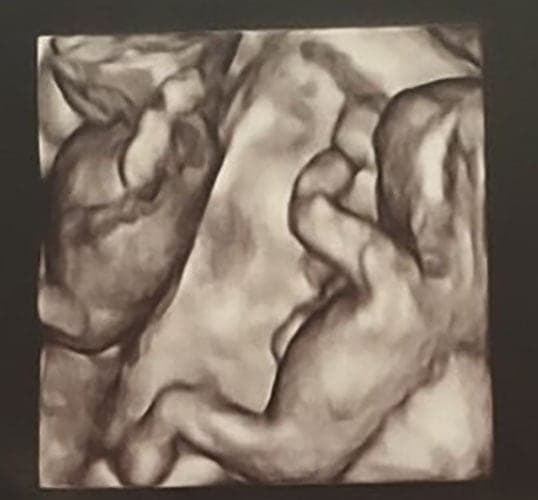

Ultraschallbilder aus dem 3. Trimester (29. bis 40. SSW)

Im dritten Trimester der Schwangerschaft ist das Baby so groß, dass es nicht mehr komplett auf ein Ultraschallbild passt. Nun kann man wunderbare 3D-Ultraschalle des Gesichts machen. In diesem Semester nehmen die Babys nochmal rasant zu und wer Glück hat, kann auf seinem Ultraschall schon erste Gesichtszüge erkennen.

Wer sich jedoch erhofft Gesichtszüge zu erkennen, der wird oft enttäuscht. Zwar kann man beim 3D-Ultraschall schon eine Menge sehen, aber das umgebende Fruchtwasser sorgt in den allermeisten Fällen für starke Störungen.